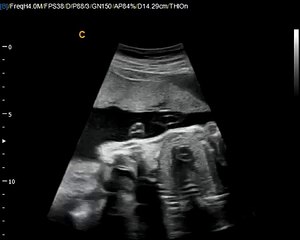

Q5 by Chison imaging Fetal Heart sonogram, easy to see heart in fetus, neonatal ultrasound